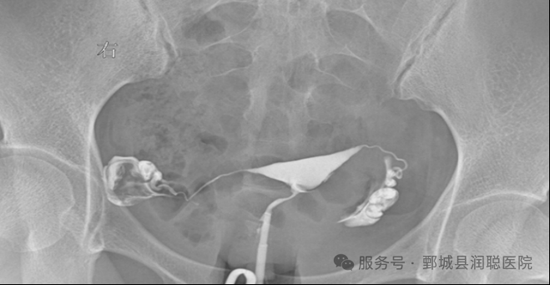

子宫输卵管碘油造影(hysterosalpingography,HSG)在X线透视下进行,通过导管向宫腔内注人碘油或碘水,并在不同时段进行摄片,以了解造影剂弥散在盆腔内的情况。

不仅能了解输卵管是否通畅,而且可以了解输卵管阻塞部位,以及子宫和输卵管的形态,是目前评价输卵管通畅性zui好的试验和首 选的方法。

4.图像清晰直观, X光片能提供非常清晰、静态的宫腔形态和输卵管全程显影图像(如输卵管是否扭曲、扩张、积水),对宫腔粘连、畸形、输卵管积水等病变显示效果好。